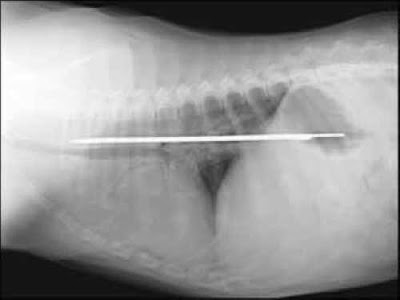

Most Shocking X-Ray

you can never seen this types of X-rays Pics Before its unbelievable and amazing x-ray pics.